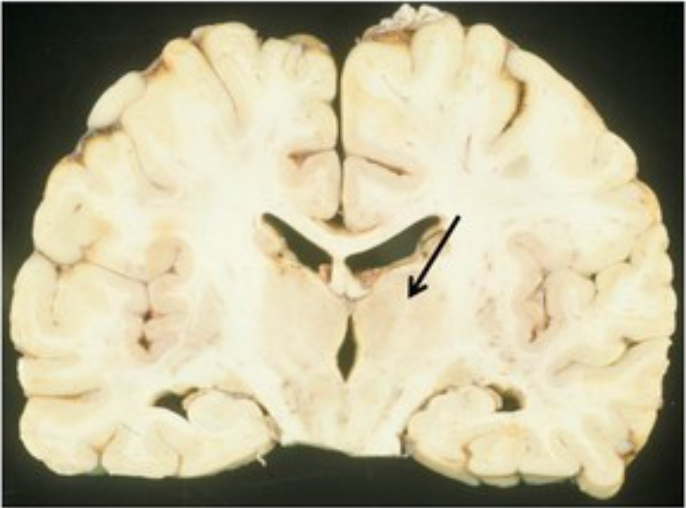

Identify

thalamus